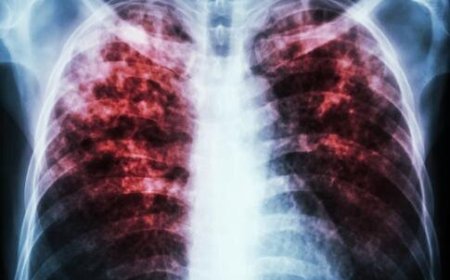

آیا رژیم غذایی می‌تواند جایگزین واکسن سل شود؟

رژیم غذایی سالم می‌تواند عفونت‌های ناشی از بیماری سل را تا ۵۰ درصد کاهش دهد.